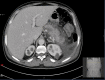

Figure 1

CT of the abdomen showing an acute pancreatitis with diffuse parenchymal enlargement, indistinct pancreatic margins and focal necrosis.